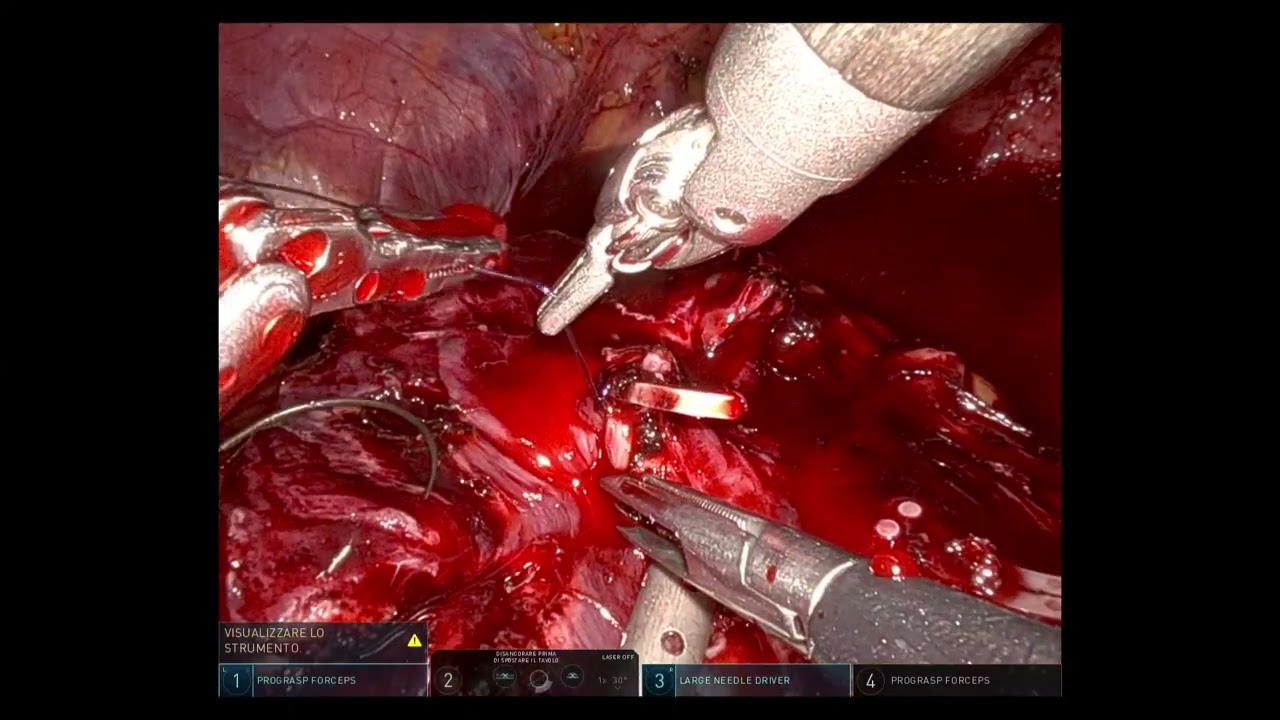

#306 Single port urinary diversion in a hostile abdomen- Dr. Neerja Tillu

KS Awards, Robotics, Surgeon ';